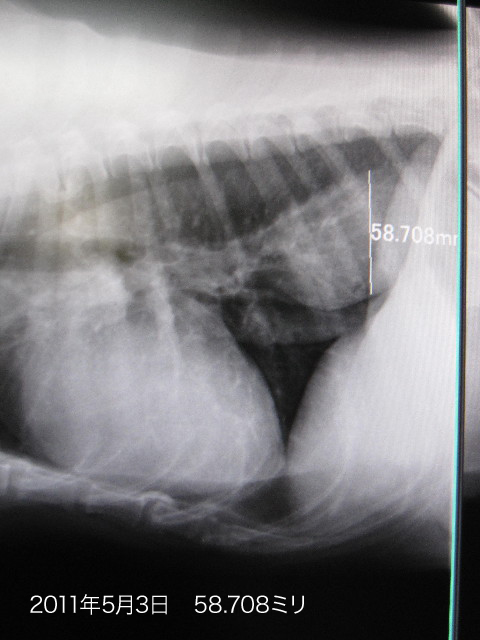

4ケ月ぶりにレントゲンを撮ったら

●哀しいかなべべちゃんのnQちゃんの直径が6.861ミリも大きくなってしまっていました。。。。

(1月4日は51.847ミリ/5月3日は58.708ミリ)

色々頑張っているのに、Qちゃんは少しずつ大きくなってしまっているのね(哀)

いつか手術も視野にいれないとならないかも?しれないけれど、今はまだ吐出しないのでこのまま様子をみましょうってことに。

Qちゃんが大きくなっていたのはショックだったけど(こんな時だから被爆を少しでもさけるためにあえてレントゲンを撮らないでいたの)、弱気になんてなってないよ!